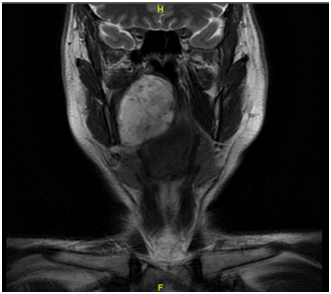

A 42 year old male, with no previous medical history was referred to the Otorhinolaryngology and Head & Neck surgery outpatients’ department at Mater Dei Hospital with Obstructive Sleep Apnoea (OSA) symptoms. The patient admitted to a few year history of such symptoms. During examination, a large right sided lesion was seen in the oropharynx which seemed to be arising from the soft palate. This lesion was seen to be crossing the midline and most likely contributing to his obstructive symptoms. The patient underwent a flexible nasoendoscopy which showed a large lesion extending to the lateral nasal cavity. Subsequently the patient underwent urgent imaging with computed tomography (CT) (Figure 1) of the neck and thorax which showed a large mass with the most likely site of origin being in the right tonsillar bed. A dedicated magnetic resonance imaging (MRI) (Figure 2) (Figure 3) of the neck was recommended for staging, to better assess the extent of the lesion. Two hypoechoic intrahe-patic liver lesions were discovered were also noted. A biopsy of the lesion arising from soft palate was taken under local anaesthesia which was reported as adenomatoid acinar hyper-plasia.

Figure 2 Coronal MR scan showing a large right sided parapharyngeal lesion causing incomplete upper airway obstruction.